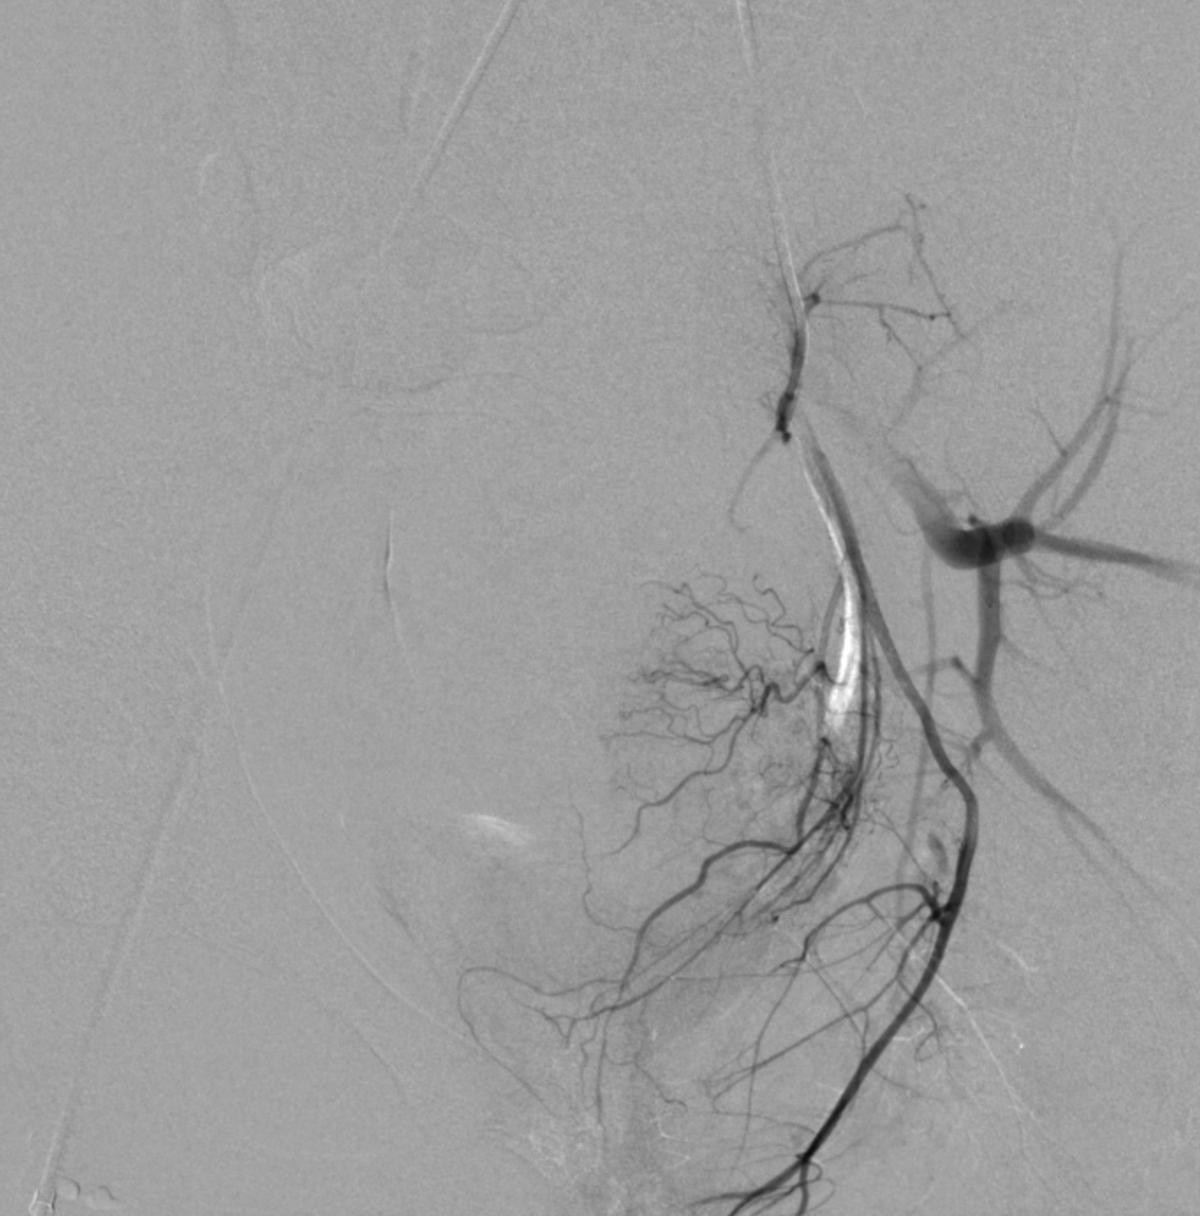

患儿完成入院前术前检查,并进行了全科的术前讨论。结合患儿体征及相关的术前检查,目*考前**虑PROS综合症。目前主要解决的是月经出血的问题,可以通过栓塞双侧子宫动脉来进行治疗。患儿全麻后,使用5F穿刺针行右股动脉穿刺,成功后置入5F血管鞘,导丝引导下置入5F Headhunter Angiopointer造影导管,在导丝引导下选入髂内动脉,进入子宫动脉,造影见左侧子宫动脉远端纤细,右侧子宫动脉螺旋增粗,微导丝引入微导管进入子宫动脉,使用聚乙烯醇颗粒栓塞剂350um-560um,栓塞微粒球(300-500um)分别行双侧子宫动脉栓塞,栓塞后造影未见子宫动脉远端分支显影。

左侧子宫动脉远端纤细

右侧子宫动脉造影